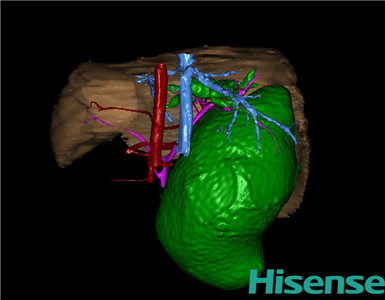

术前三维重建及手术方案设计:

将0.625mm双源薄层CT资料的静脉期和动脉期Dicom格式文件导入海信CAS系统。

通过调节窗宽窗位调整CT序号,对肝实质,胆囊,胆总管,下腔静脉,肝动脉、门静脉及肝静脉等进行三维重建;系统自动计算肝脏体积。

术前三维重建:

重建图片